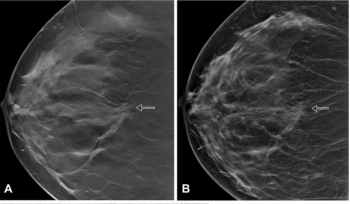

In separate test sets of Israeli women and United States women who had either ductal carcinoma in situ or invasive breast cancer, emerging artificial intelligence (AI) algorithms achieved an area under the curve (AOC) of 88 percent and 80 percent, respectively, for malignancy detection.